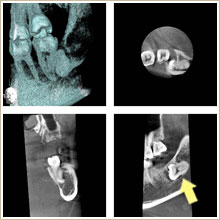

ケース1

下顎の親不知の歯が横向きになって顎骨の中に深く埋まっています。

手前の第2大臼歯に悪影響を及ぼしているため、抜歯をすることになりました。

次に、安全な抜歯を行うために、CTレントゲンを撮影しました。

矢印で示す大きな神経や血管のある下顎管が、親不知に近接しています。

このまま抜歯すると、下顎管を傷つけ、併発症を引き起こす可能性があるため、矯正抜歯を行うことにしました。

埋まっている親不知の表面を出し、ゴムを取り付けて引っ張る力を加えます。

1ヶ月後に抜歯を行いました。

抜いた歯です。